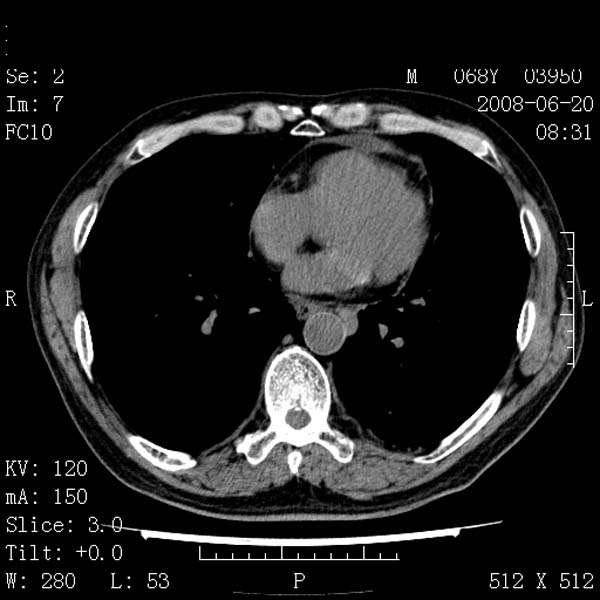

以下是引用zjzjr在2008-6-24 11:19:00的发言:[br]支持左下肺周围型肺癌伴右肺转移,纵隔淋巴结转移,心包积液.

以下是引用zhangling在2008-6-24 14:56:00的发言:[br]我们科室意见报告为[br][br]1考虑左下肺周围型肺癌[br]2右肺小结节考虑转移瘤,纵隔淋巴结转移[br]3心包积液. [br] 各位老师分析的相当好 谢意[br]